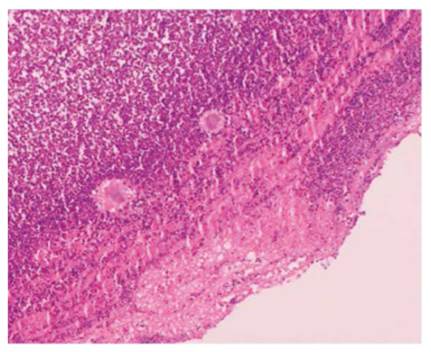

Se dio continuidad a manejo antibiótico a 8 semanas. Posteriormente presenta nuevo pico febril que se asoció a coinfección por virus de SARS COV2 confirmado por PCR. Posteriormente se recibió reporte de biopsia de líquido pleural con hallazgos compatible con Actinomyces spp. (Fig.3 y 4).

Figura 3 Coloración de Hematoxilina-eosina, aumento 10X. Líquido pleural con proceso inflamatorio agudo severo y presencia de estructuras redondeadas por bacterias “Signo gránulos de azufre”